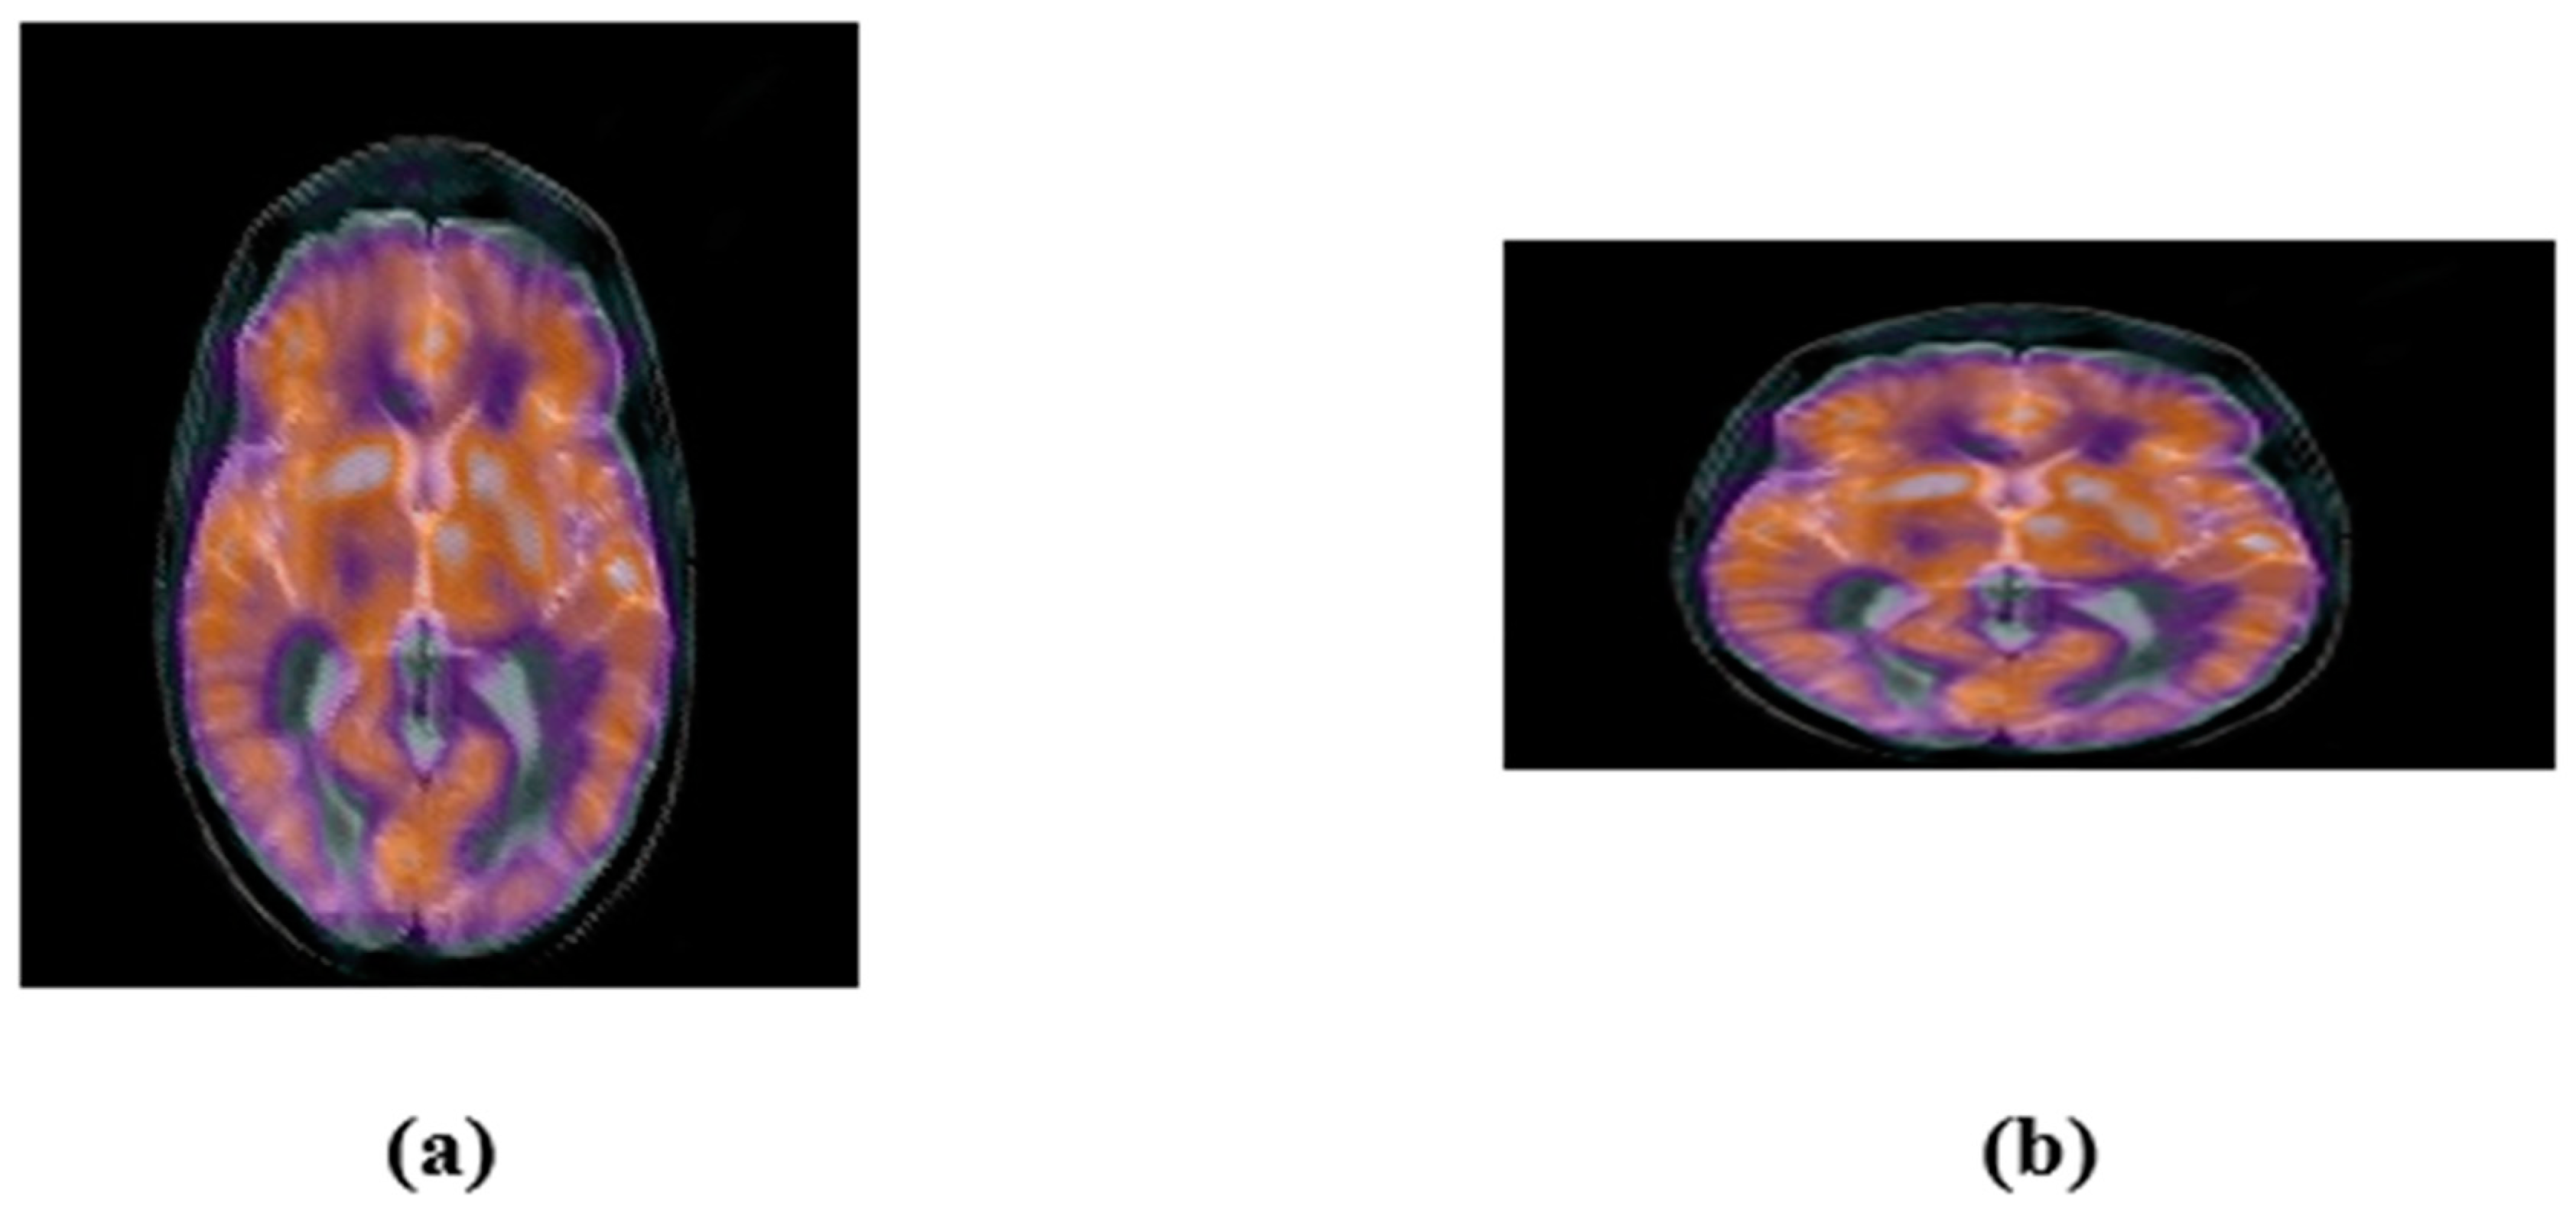

4.2.2. Geometric Attacks

| Applied Attack | LWR (1.0, 0.75) | LWR (0.5, 1.0) | Horizontal-flipping | Vertical- Flipping |

| Extracted watermark | ![]() | ![]() | ![]() | ![]() |

| BER | 0.0049 | 0.0068 | 0.0010 | 0.0010 |

| NC | 0.9892 | 0.9849 | 0.9979 | 0.9979 |